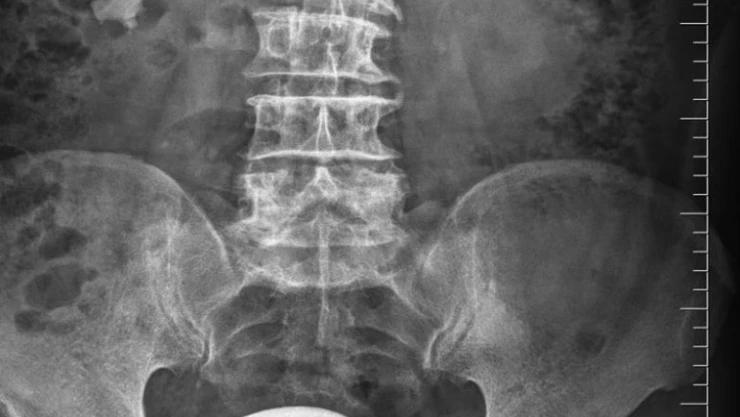

Ordu'nun Fatsa ilçesinde idrar yolu enfeksiyonu bulunan hastanın mesanesinden büyük boy patates yumrusu kadar taş çıkarıldı. Sürekli idrar yolu enfeksiyonu olan ve dayanılmaz idrar yanması, sık idrara çıkma ve idrar tutmakta zorlanması olan hasta ilaç tedavilerinden fayda görmemesi üzerine Fatsa Devlet Hastanesi Üroloji Polikliniği de Opr. Dr Yüksel Şahin'e başvurdu. Yapılan tetkik ve tahliller sonucunda hastanın mesanesinde çok büyük bir taş saptandı.

Literatürde bu boyda taş görülmesi çok nadir karşılanırken hastanın mesanesinden çıkan taş şaşkınlıkla karşılandı. Derhal ameliyata alınan hastanın mesanesindeki taş kapalı yöntemle çıkarılması mümkün olmadığından açık sistolitotomi ameliyatı yapıldı. Herkesi şaşkına çeviren büyük bir patates yumrusu şeklindeki taş başarılı şekilde alındı.